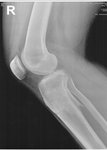

рентген в 60 дней.

Сращение идёт хорошо. Делаем рентген в 90 дней и готовимся к снятию.